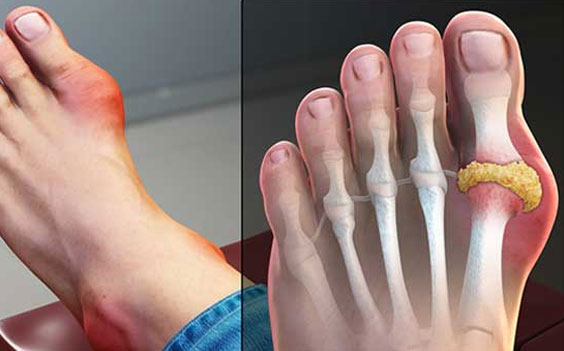

Gout

Gout is a condition that often affects your feet, especially in the big toe, because of too much uric acid in your body. The affected area may feel very painful. Some describe the pain as feeling like your foot is on fire.

This condition occurs in many forms and in four stages. You may experience gout that comes and goes or develop more chronic gout over time that damages your joints.

Gout can be aggravated for many reasons, such as from eating certain foods, and occurs most commonly in men between 40 and 50 years old and in postmenopausal women.

Your doctor should treat gout and may recommend healthy lifestyle habits to manage symptoms.